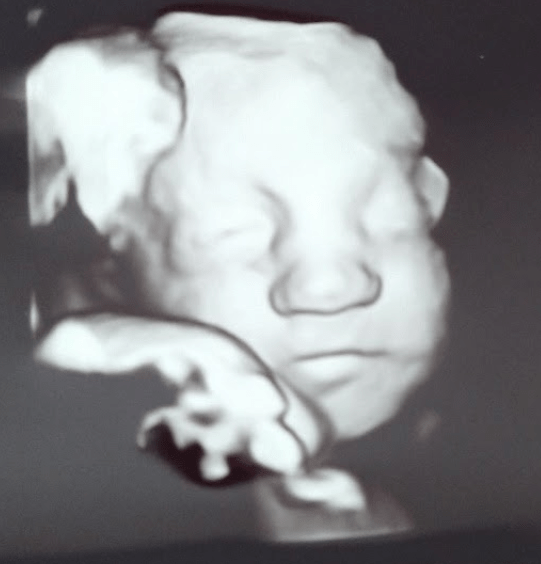

Now, my wife and I did things a little backward from how most folks do them these days. We knew we were having a high-risk pregnancy (namely due to only having one umbilical artery instead of the typical two) and so we were offered a range of genetic testing options that we could pursue. However, we chose not to do any testing because we knew that there was nothing we could do about any of it anyways—and none of it was going to impact our stance or our love for our child. We recognized that we were not in control of anything—especially in regard to how our unborn daughter was developing in the uterus. And we knew that there was nothing we could do from outside the womb that would change whatever was going on inside the womb (even though Katie did receive extremely painful steroid shots directly into her hind parts for the last few weeks of her pregnancy because there was a slim chance that they would help boost our unborn child’s defenses and growth. Mothers are truly rare and remarkable sacrificial creatures. Being the dad, I was never offered any glute steroids. I also didn’t ask…). It was all in God’s hands regardless of whether we had any clear diagnosis before delivery or not.